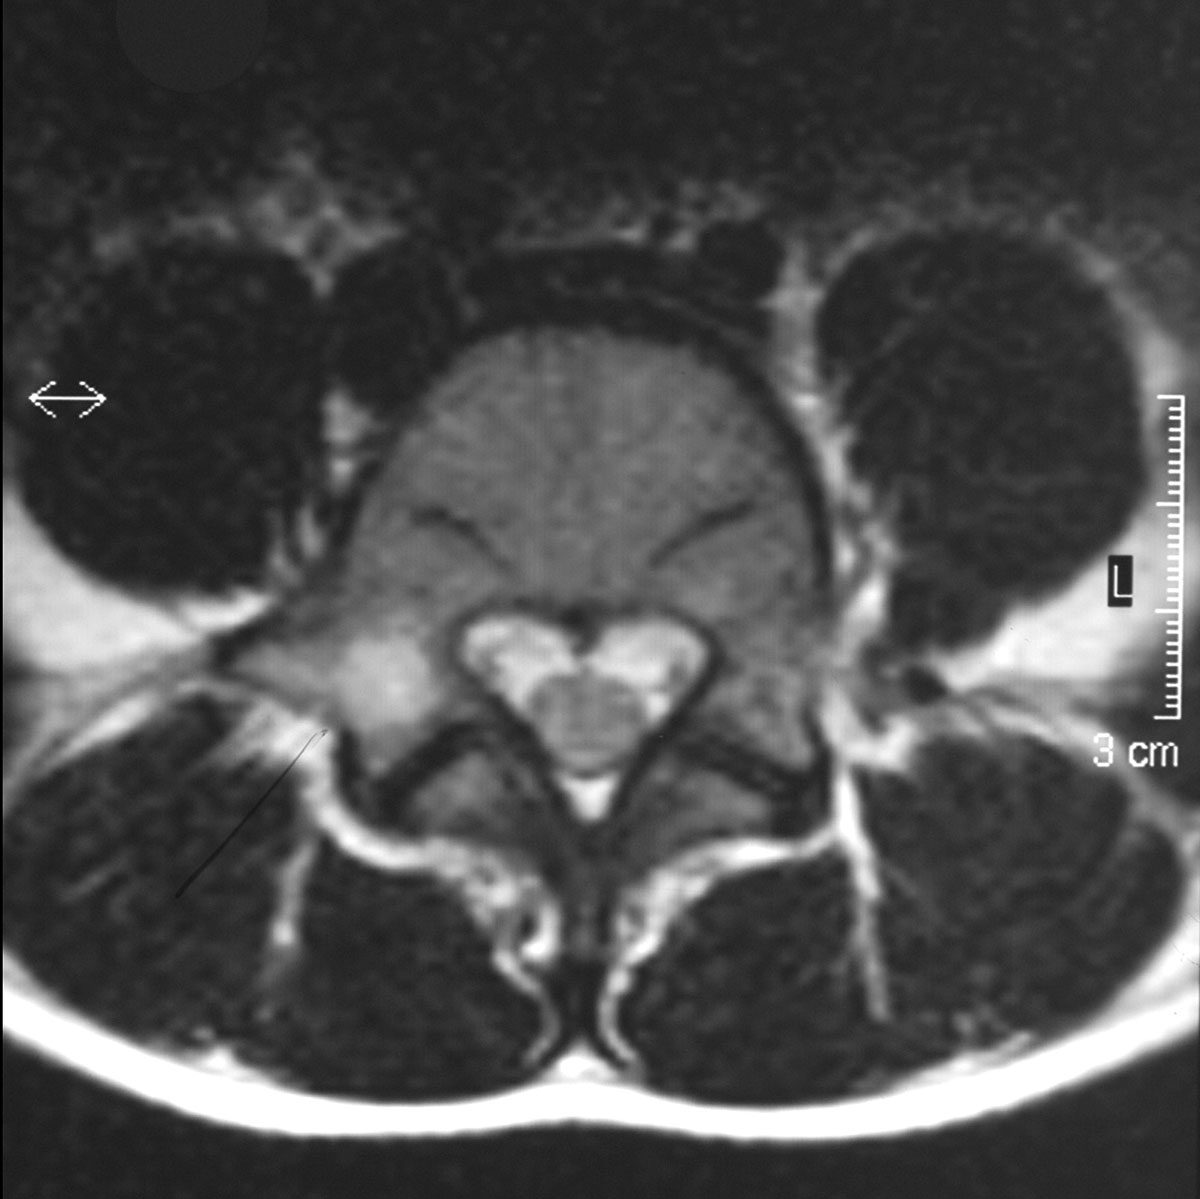

Eine Alternative stellt die Dünnschicht-CT des betroffenen Wirbelkörpers dar. Es ist auf eine entsprechende Gantry-Kippung zu achten, um diese Spondylolyseregion orthograd zu treffen (Abb. 2b + 3). Eine Kernspintomographie kann ebenfalls dienlich sein, hier finden sich typischerweise bone-bruise-artige Veränderungen in den T2- und STIR-Wichtungen, die Unterbrechung in der Interartikularportion ist jedoch kernspintomographisch nur schwierig zur Darstellung zu bringen (Abb. 2a). Die Kernspintomographie stellt am besten den Degenerationsgrad des betroffenen Bandscheibenfaches und mögliche neuroforaminale Engen dar. Der diagnostische Algorithmus sollte somit primär eine konventionelle Röntgenaufnahme in 2 Ebenen beinhalten. Bei anhaltenden Beschwerden ist eine Kernspintomographie und bei fehlendem Nachweis eines Korrelates für die bestehende Symptomatik eine Dünnschicht-CT zum Nachweis oder Ausschluss der Spondylolyse indiziert. Eine Drei-Phasen-Skelettszintigraphie oder ein SPECT/CT können in Ausnahmefällen ebenfalls als diagnostisches Mittel Einsatz finden, sollten jedoch aufgrund der Strahlenbelastung nur in ausgewählten Fällen zum Einsatz kommen.